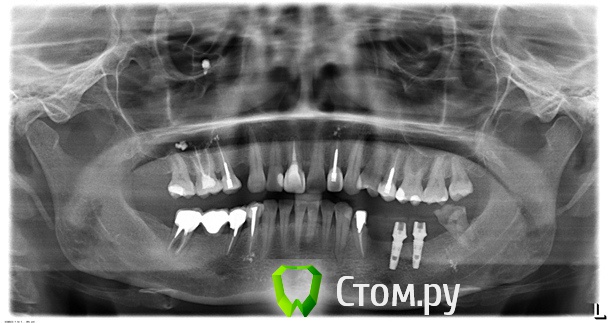

A_ALEX1_A Опубликовано 9 февраля, 2014 Автор Поделиться Опубликовано 9 февраля, 2014 Попробовать можно, тогда нужно убрать имплантат, поместить в лунку имплантата костный заменитель и все гермитично зашить и молиться через 4-6 мес провести повторную установку имплантата. Если молитвы окажутся действенными Добрый вечер ув.врачи! Немного истории чтобы не перечитывали ветку. Имплантация прошла 6 агуста установили 3 импланта, с 5 -7 на нижнюю челюсть слевой стороны. Однако 1 имплант на месте 5 зуба установлен был очень близко к 4-ке, его выкрутили 5 октября. Слава богу зуб не пострадал, все в норме. Мне сделали временные коронки которые сейчас от нагрузки поламались, к "своему" имплантологу нет возможности пойти так как нахожусь в др. городе. Была у др. имплантолога, который дал несколько вариантов: 1) Не устанавливать имплант и сделать постоянные коронки в виде моста начиная от депульпированной 4-ки и захватив 2 импланта2) 8-ка у меня разваливается, но есть антогонист, поэтому второй вариант предложил установить имплант вместо 8-ки и так же сделать мост с 4-8. по поводу этих вариантов, читала отзывы врачей на форуме что нельзя объединять в мост зуб и импланты, или в моем случае это возможно? 3) установить имплант на месте 5 зуба и сделать коронку на 3 импланта с 5 по 7, а 8-ку просто удалить. и еще вопрос в случае 3 варианта лучше сделать коронку на 3 импланта, либо надо сделать отдельные коронки на каждый имплант...хотелось бы сделать так как будет лучше..но как лучше не знаю. Помогите, пож-та, советом. Снимок от 8.02.14г. Ссылка на комментарий

Bier Опубликовано 10 февраля, 2014 Поделиться Опубликовано 10 февраля, 2014 мне больше по душе 3й вариант. Коронки скорее всего можно и раздельные, но там надо смотреть уже на модели, в каких позициях имплантаты стоят. 1 Ссылка на комментарий

A_ALEX1_A Опубликовано 11 февраля, 2014 Автор Поделиться Опубликовано 11 февраля, 2014 мне больше по душе 3й вариант. Коронки скорее всего можно и раздельные, но там надо смотреть уже на модели, в каких позициях имплантаты стоят.а по сроку и состоянию кости можно ли уже имплантировать, либо еще надо подождать...??? Ссылка на комментарий